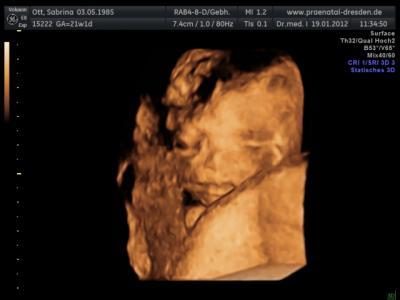

So nun werde ich euch mal meinen Bericht abgeben! Also Baby geht es super er meinte zwar er ist klein und sehr ziehrlich aber ich bin ja auch nicht die Größte und krägtigste da wäre es ok! Es wiegt ca 354 g und ist 25 cm groß :-). Alles aber gut Zeitentwickelt und alle Organe, das Herz und das Gehirn sind sehr gut entwickelt :-) Das einzigste was nicht so gut ist ich habe zu wenig Fruchtwasser deswegen muss ich in 4 Wochen wieder hin um das noch mal zu kontrollieren! Weiß nur nicht was das bedeutet hab ihn zwar gefragt aber er wollte mir nix genaues sagen nur halt das es ni weniger werden darf und da hab ich ihn halt gefragt was dann passiert bzw passieren kann da meinte er nur das besprechen wir falls es sein wird wir warten erst mal 4 Wochen! Kennt sich jemand da aus? Was passiert dann? Wie bekomme ich mehr? Wird es überhaupt mehr? Foto war leider nicht so einfach Krümel hat sich mit dem Gesicht im Mutterkuchen versteckt aber der Doc hat sein möglichstes gegeben :-) Ja und ihr habt richtig gelesen "er" Junge ist nun bestätigt, hatte noch ein bißchen Hoffnung das es doch ein Mädchen wird aber nun gut jetzt freut sich mein Großer auf einen Bruder grins glg

Bild zu Bericht von der Feindiaknostig - Forum für Juni - Mamis